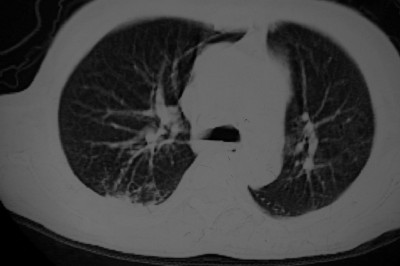

以下是引用天南地北在2007-4-10 1:49:00的发言:[br]考虑右下叶周围型肺癌伴肋骨转移。

以下是引用jone-baby在2007-4-10 8:45:00的发言:[br][br] [br] 患者[br]有发热史,x线片考虑肺脓肿.肺脓肿可以导致肋骨破坏吗?[br]脓肿可以排除吗? [br] [br] [br]

以下是引用林建春在2007-4-10 7:35:00的发言:[br]周围型肺癌侵犯肋骨

以下是引用liuyue在2007-4-10 7:56:00的发言:[br]周围型肺癌侵犯肋骨,左肺转移。

以下是引用zhangzhongshou在2007-4-10 10:24:00的发言:[br]右肺下叶背段厚壁空洞,伴胸膜改变、肋骨破坏,其内可见死骨、周围骨质硬化,左肺可见小结节影,[br]单纯影像学更支持结核。建议进一步检查。